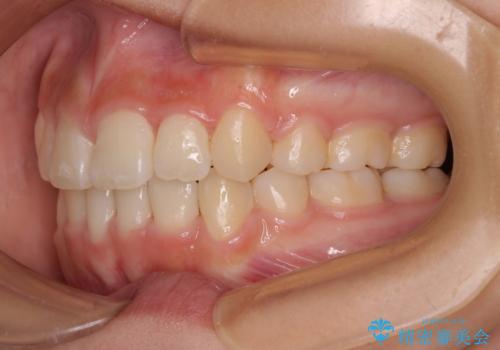

- 歯列全体の叢生を気にして来院された患者様です。

検査を行った結果、上顎骨の横幅が相対的に狭いことが分かり、叢生が強いことから、急速拡大装置にて上顎骨を側方に拡大することで、叢生の解消と奥歯の咬み合わせ改善を図ることとしました。

一般的には上下左右の第一小臼歯4本を抜歯する必要がありますが、拡大量によっては非抜歯矯正の適用となる可能性があるため、まずは非抜歯矯正で治療を開始し、抜歯が必要と判断された時点で速やかに4本抜歯を行うこととしました。

急速拡大後、歯列はきれいに並んだのですが、口元が出っ歯になってしまったため、速やかに抜歯を行い、治療期間がいたずらに遅延することのないようにしました。